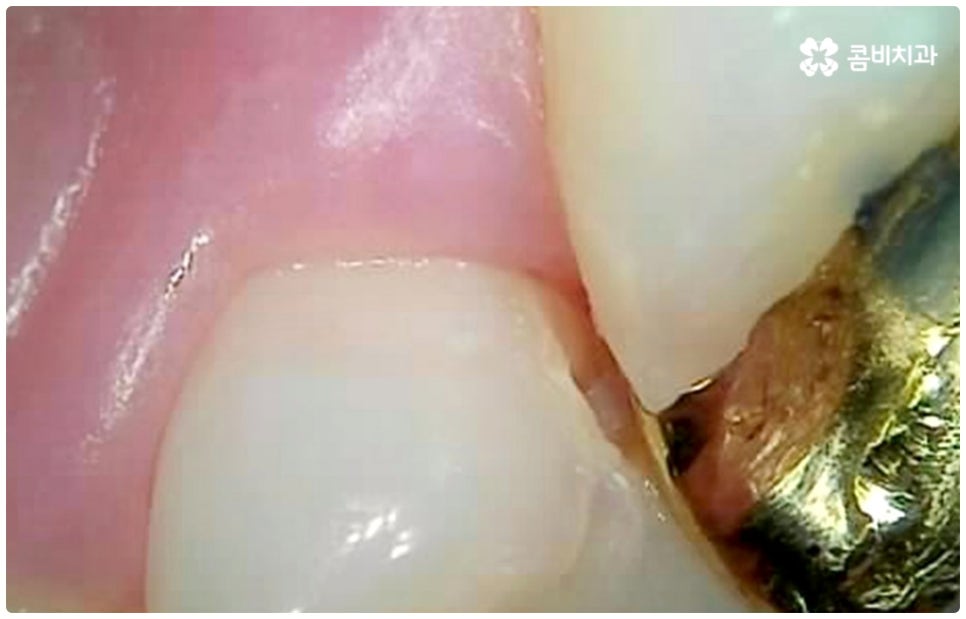

그렇기 때문에 많은 분들이 일반적으로 시린 통증을 느낄 때 치과를 방문하게 되는데, 이 때는 이미 충치균이 치아의 단단한 겉면인 법랑질을 뚫고 상아질까지 침투한 단계일 가능성이 높으니 더 늦기 전에 바로 필요한 처치를 해 주실 필요가 있습니다. 상황에 따라 다르지만 보통 이 단계에서는 레진으로 직접 때워주는 치료가 적합하지 않은 경우가 많기 때문에 그럴 때는 충치치료종류 중 인레이 온레이와 같은 보철물을 이용하여 도움을 받을 수 있는데요. 이러한 치료는 손상된 부위를 깔끔하게 삭제한 후에 그 범위와 정도에 따라 빈 공간에 맞춤 제작한 보철물을 채워넣는 것으로 (인레이는 상대적으로 깊고 좁은 부위에, 온레이는 교두를 포함한 좀 더 넓은 부위에 적용), 재질 역시 다양한 가운데 치아의 위치 및 역할, 그리고 환자분들의 경제적 상황 등 여러 가지를 고려하여 가장 잘 맞는 것으로 선택하면 되니 꼼꼼한 검진 후 담당의 선생님과 각 재질의 장단점에 대해 사전 상담을 충분하게 해 보시고 신중한 결정을 내리시길 권유드리고 있어요.